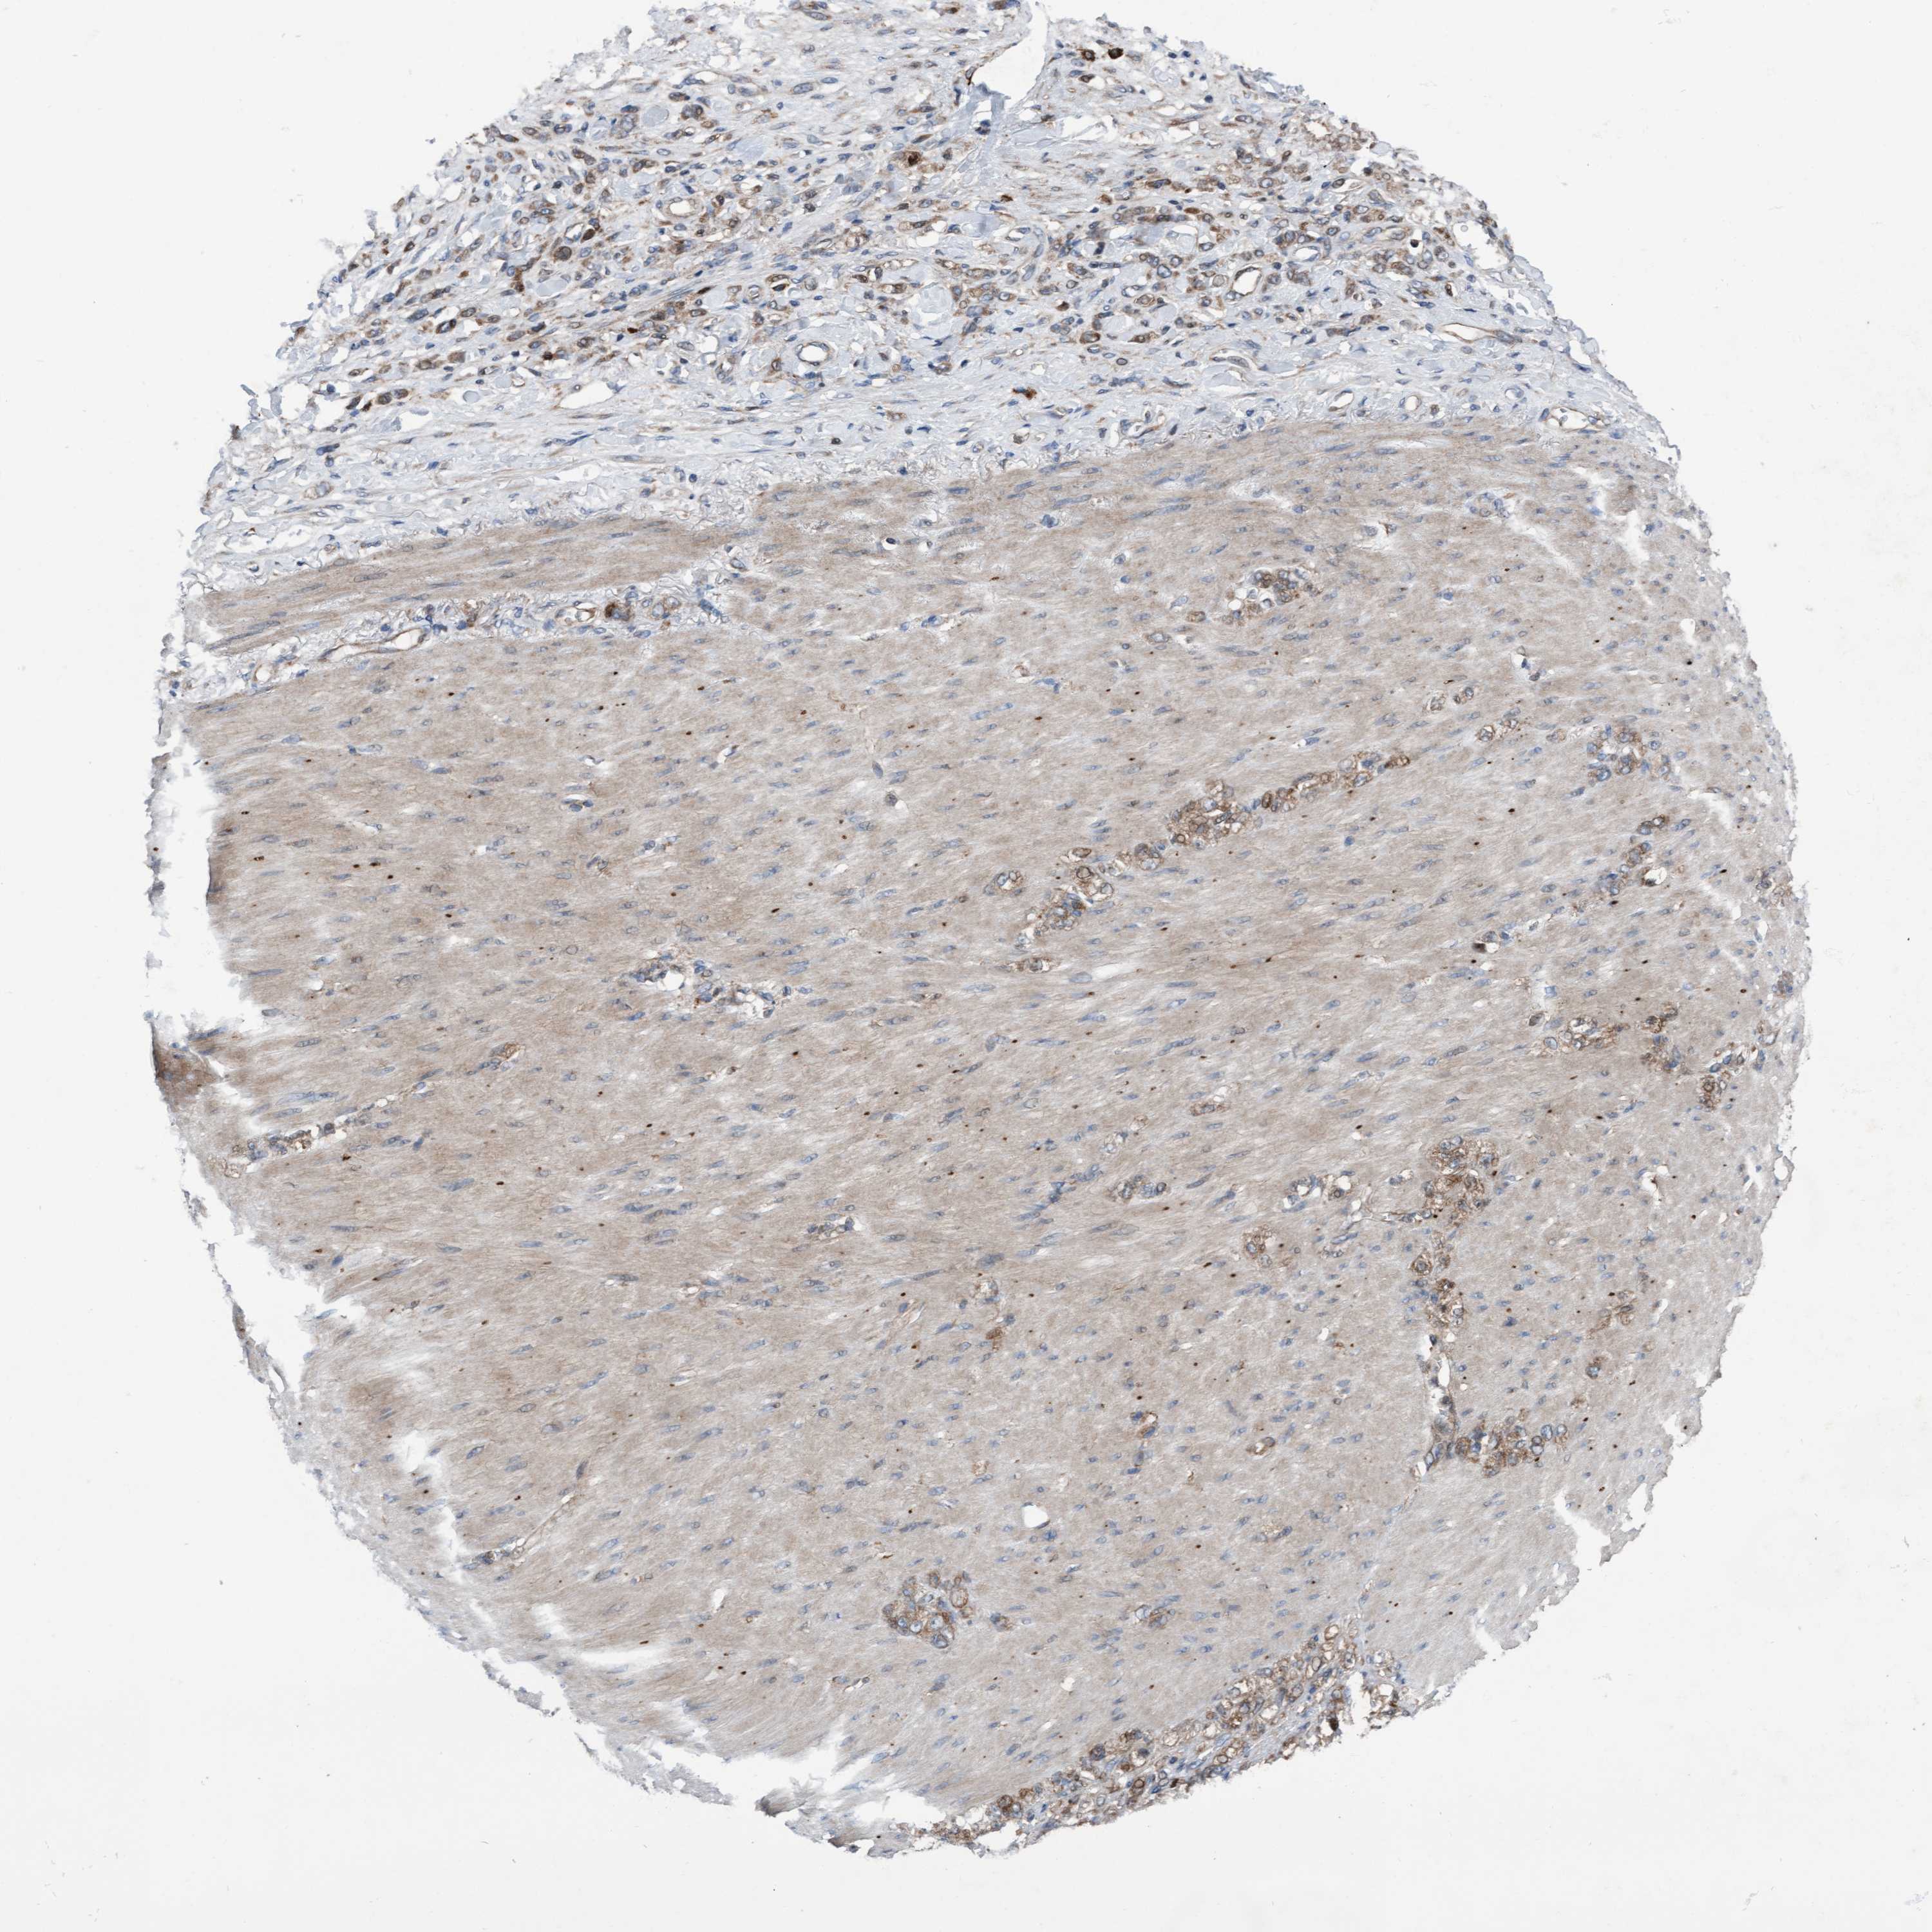

STOMACH CANCER - Protein expressioni

A mouse-over function shows sample information and annotation data. Click on an image to view it in a full screen mode. Samples can be filtered based on level of antibody staining by selecting one or several of the following categories: high, medium, low and not detected. The assay and annotation is described here.

Note that samples used for immunohistochemistry by the Human Protein Atlas do not correspond to samples in the TCGA dataset.

Antibody stainingi

Antibody staining in the annotated cell types in the current human tissue is reported as not detected, low, medium, or high, based on conventional immunohistochemistry profiling in selected tissues. This score is based on the combination of the staining intensity and fraction of stained cells.

Each image is clickable and will lead to virtual microscopy that enables deeper exploration of all samples and also displays staining intensity scores, fraction scores and subcellular localization as well as patient and tissue information for each sample.

Antibody HPA023074

Staining

High

Medium

Low

Not detected

Intensity

Strong

Moderate

Weak

Negative

Quantity

>75%

75%-25%

<25%

None

Location

Nuclear

Cytoplasmic/membranous

Cytoplasmic/membranous,nuclear

Adenocarcinoma, NOS